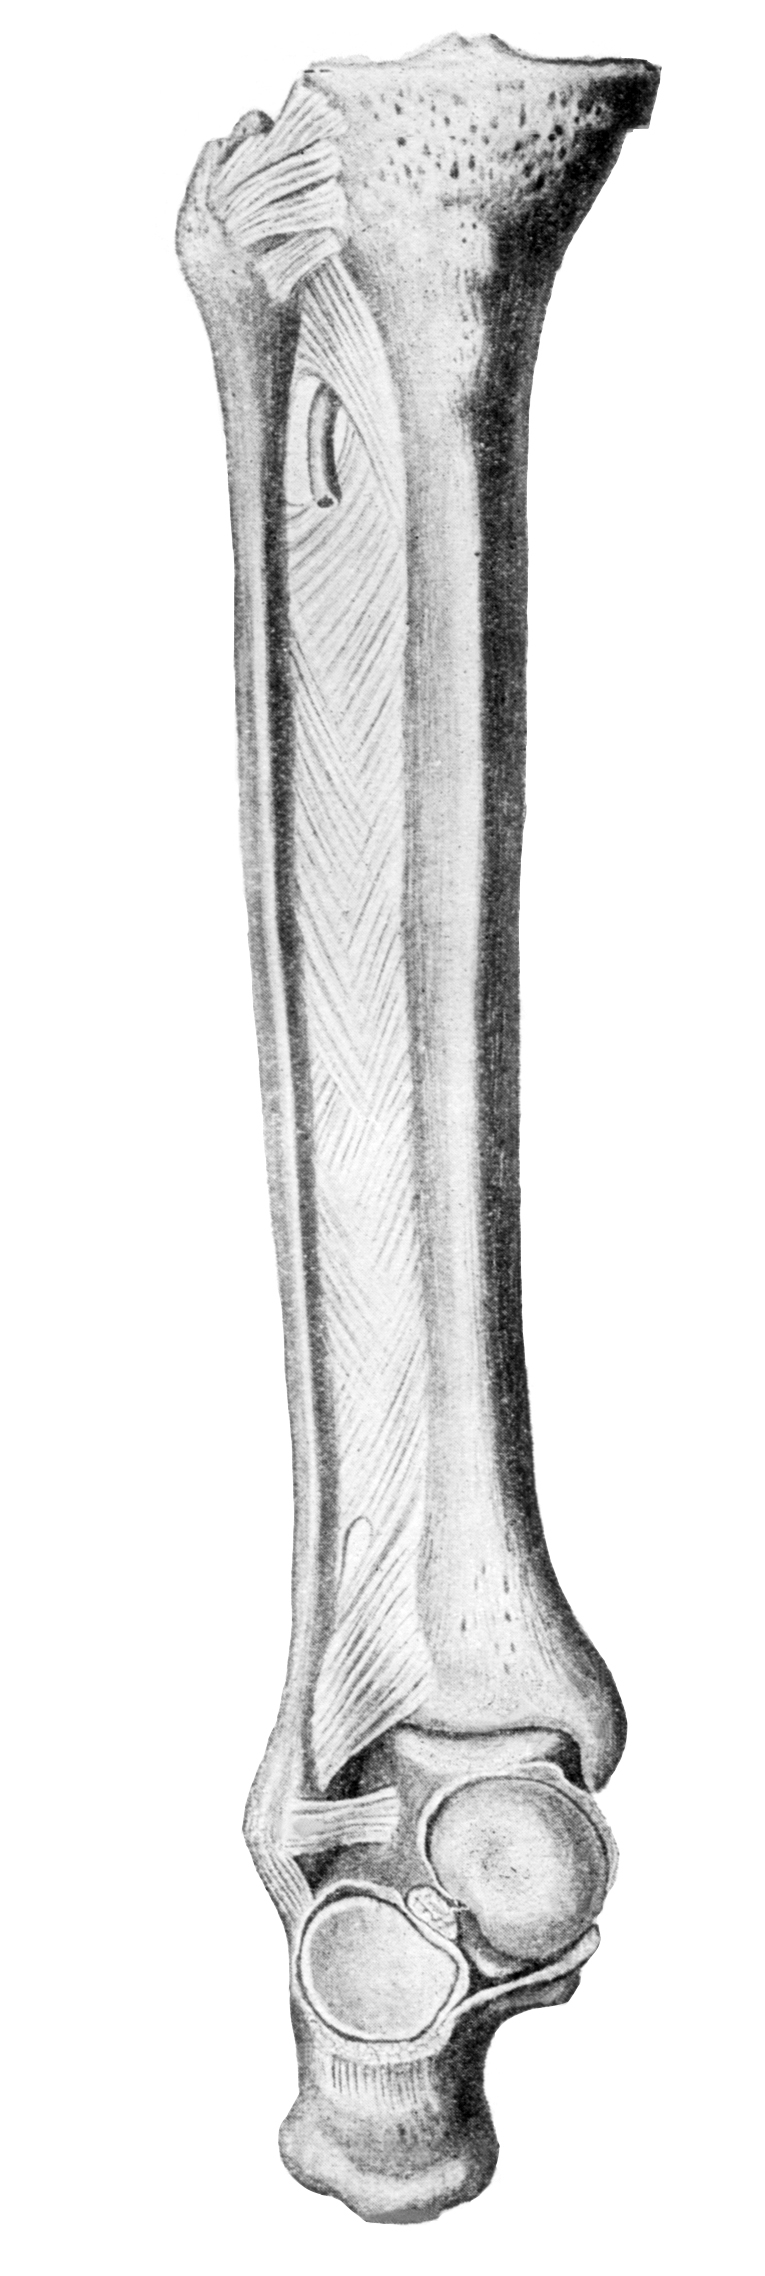

Анатомия фибулы: Подробные фотографии и схемы